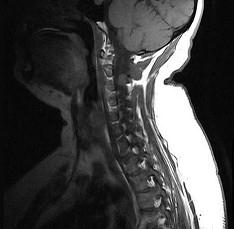

问题 关于椎管内肿瘤(如图所示)发生,下述哪项最不正确()

选项 A.脊髓髓内肿瘤多为胶质瘤 B.脊髓髓内肿瘤最为常见 C.脊髓髓外硬膜下病变最常见的是神经鞘瘤 D.硬脊膜外肿瘤以转移性肿瘤最多见 E.发病率以胸段最常见

答案 B